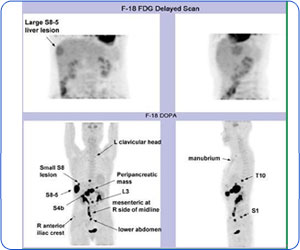

F-18 DOPA掃描顯示出多處神經內分泌瘤病灶。